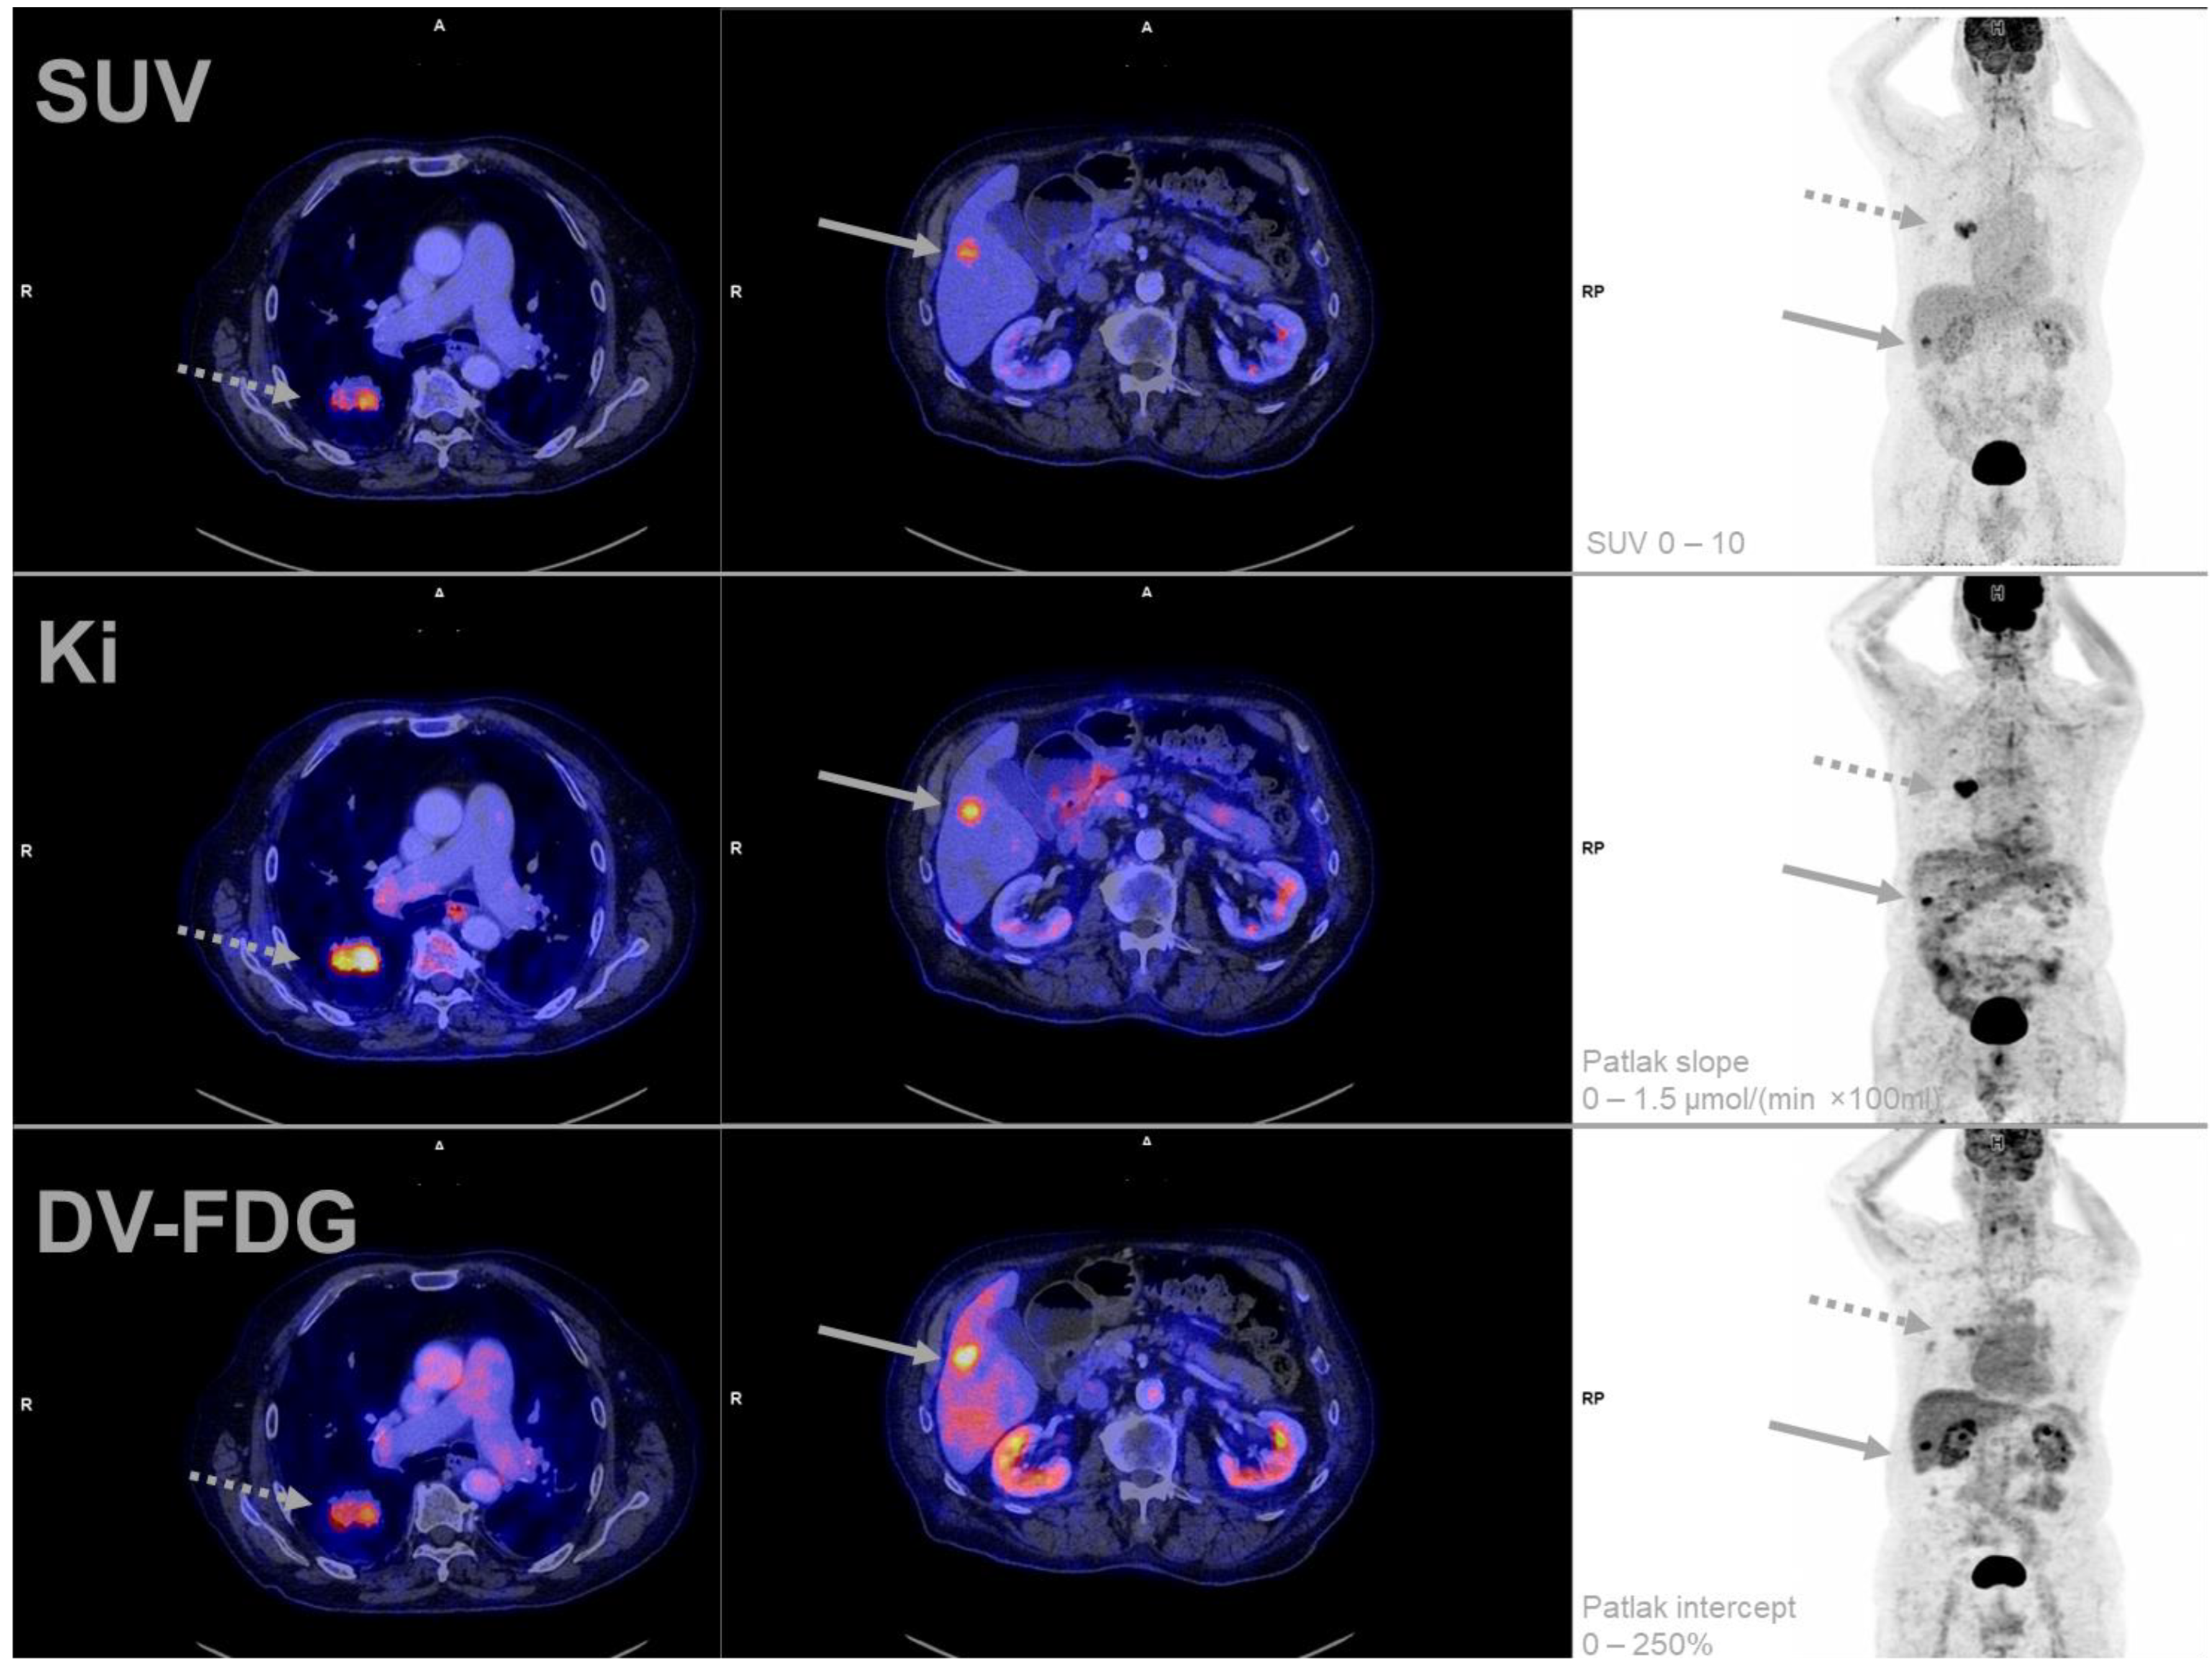

All patients tolerated the complete scheduled acquisition time. No examination had to be discontinued or repeated due to technical difficulties. A representative multiparametric scan is presented in Figure 2.

Figure 2.

Representative example of multiparametric [18F]FDG PET-imaging of a patient (Study-ID 33) suffering from an adenocarcinoma of the lung (dotted arrow). A single liver metastasis was detected with PET and was histologically confirmed (solid arrow). Of note is the high DV-FDG of the liver metastasis compared to the lung tumor in combination with homogeneous imaging of the surrounding tumor-free liver parenchyma. DV-FDG = Distribution Volume of FDG; FDG = Fluorodeoxyglucose; Ki = Influx Rate Constant; PET = Positron Emission Tomography; SUV = Standardized Uptake Value.

Furthermore, data on our DV-FDG measurements, which represents the combined distribution volume of free [18F]FDG in blood and tissue (reversible compartment), also revealed strong correlations with trapped [18F]FDG measured within MR-FDG and Patlak Kimean (irreversible compartment) [18]. Interestingly, the only hepatic metastasis in our cohort was visually more distinct and focal in the parametric DV-FDG image, compared to the other parametric parameters. Furthermore, this lesion presented with a remarkably higher DV-FDG value, when compared to the lung or bone metastases. One potential explanation for this effect in the liver metastasis is a previously reported increment of dephosphorylation of the trapped [18F]FDG-6P in liver tissue [18]. High dephosphorylation activity would result in less irreversible trapping and significant efflux of the initially trapped [18F]FDG-6P via the bidirectional GLUT (esp. GLUT 1) transporter out of the cell and back into plasma [18]. This would result in higher DV-FDG values since the reversible compartment also includes both free [18F]FDG in blood and tissue as well as some [18F]FDG-6P [18]. Even if the value of DV-FDG has caused some controversy [19], our data are supportive of investigations evaluating DV-FDG as a potential imaging biomarker for liver metastases.